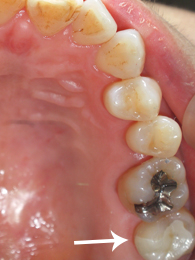

50代 女性 右上7 広陵町在住

〔術前〕